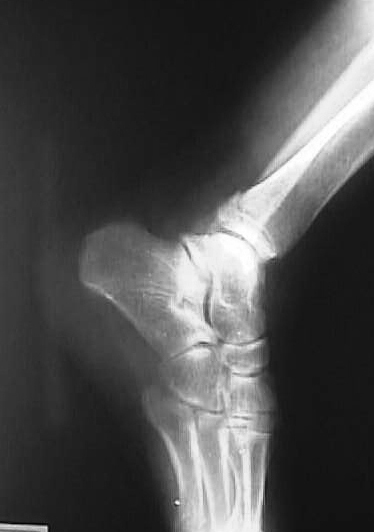

X線所見:正面像において腓骨下端部の骨折が認められ、中枢骨片の内側への転位が認められた。側面像において中枢骨片は前下方、末梢骨片は外後上方の骨片への転位が認められた。

【スライド4】

このスライドがその写真です。